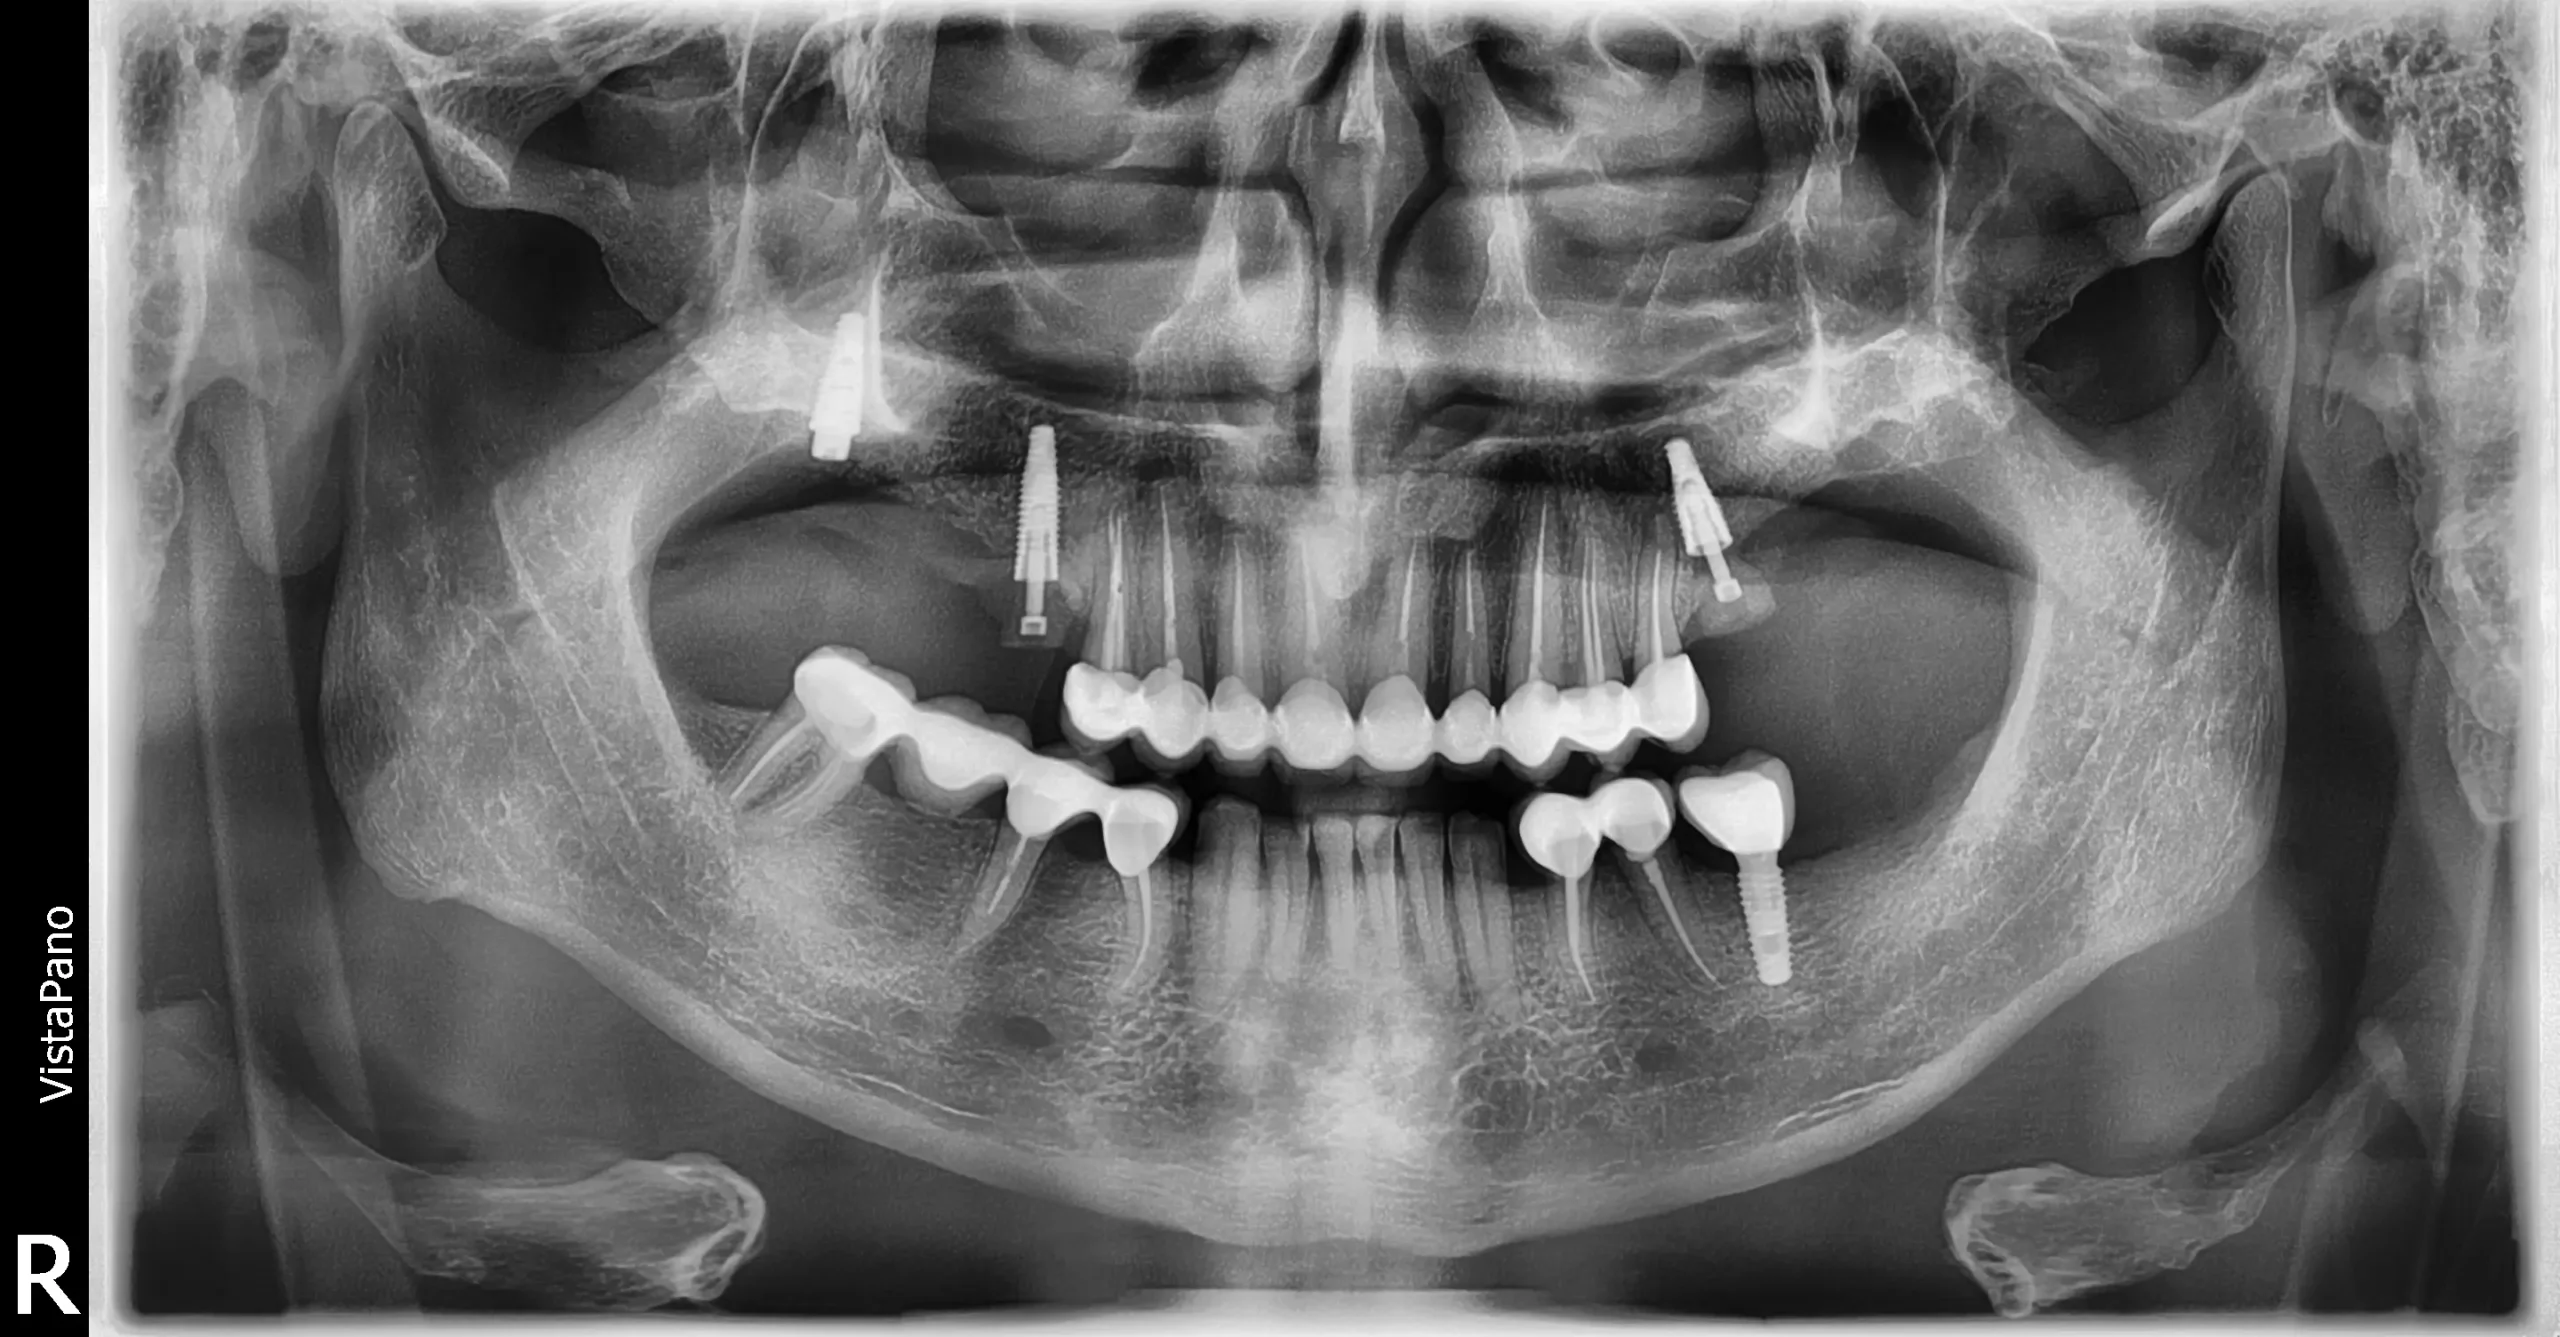

Folosind microscop endodontic, tehnologie digitală și instrumente rotative moderne, asigurăm curățarea perfectă a canalelor radiculare și o vindecare rapidă, fără disconfort.

Microscop endodontic pentru precizie totală

Fiecare canal este tratat sub mărire de până la 25x, pentru curățare completă și rezultate durabile. Utilizarea microscopului reduce semnificativ riscul apariției infecțiilor recurente

Consultația și radiografia digitală

Se realizează o radiografie pentru a evalua structura dintelui și extinderea infecției. Stabilim planul exact de tratament.